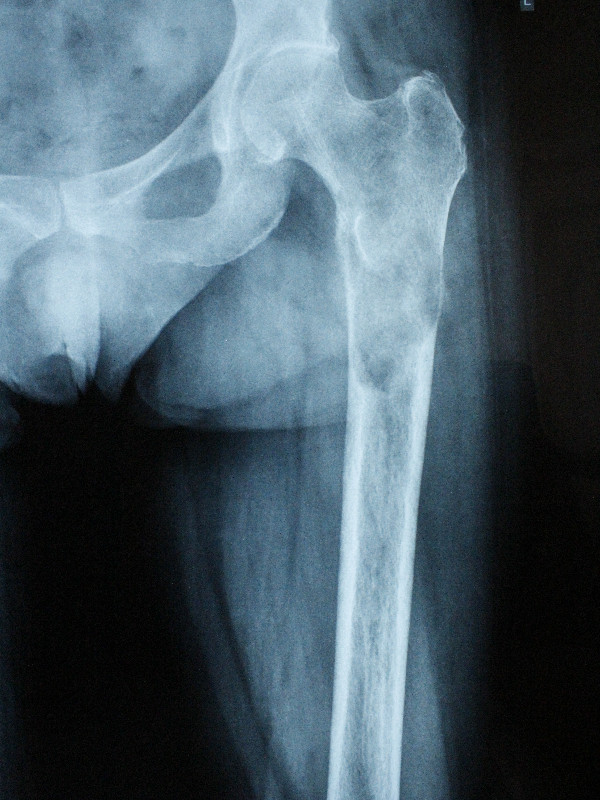

3․Մետաստազ ազդրոսկր + կոնք-ազդրային հոդ

68-ամյա պացիենտի մոտ ախտորոշվել էր թոքի քաղցկեղ։ Անցնելով համապատասխան հետազոտություններ՝ պացիենտի ոսկրային հատվածում հայտնաբերվել էին սոլիտար (եզակի) մետաստազներ: Բուժման նպատակով ՝ վերջինս ստացել է քիմոթերապիայի կուրսեր։

Հաշվի առնելով օրգանիզմի դրական պատասխանը քիմիոթերապիայի և ուռուցքի զգայունությունը դեղորայքի նկատմամբ։ Իրականացվել է ռադիկալ վիրահատություն։ Հեռացվել է ազդոսկրի վերին երրորդականը, առաջացած դեֆեկտը շտկվել է մոդուլային էնդոպրոթեզով՝ վերջույթի ֆունկցիայի կայուն վերականգնմամբ։ 68-ամյա բուժառուն ստացել է հետվիրահատական դեղորդայքային բուժում։ Վերջինս իրեն լավ է զգում։

Վիրահատությունից առաջ

Վիրահատությունից հետո